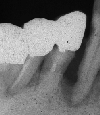

初診時のX-ray初診時

2年後のX-rayメインテナンス